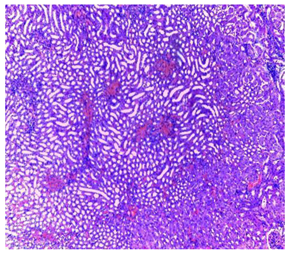

| Organ | T | EA | n-BuOH |

|---|---|---|---|

| Liver | ![]() | ![]() | ![]() |

| Hepatic parenchyma with conserved architecture | Vascular congestion, balonization of cytoplasm with clear nucleus, presence of necrosis, acidophilic bodies, basophils, small hyperchromatic nucleus, lobular lymphocyte filtrate. | ||

| Kidneys | ![]() | ![]() | ![]() |

| Round parenchyma surrounded by a fibro-adipose capsule of preserved architecture | Seat of vascular congestion with lesion of interstitial nephritis mainly made up of lymphocytes dispersed between the tubules and by sectors surrounding glomeruli. There was no objective glomerular damage on the limits of the sectors examined. Presence of surrenal gland with conserved morphology and cytology. | ||

| Lung | ![]() | ![]() | ![]() |

| A pulmonary parenchyma, made of optically empty cavity (alveoli) separated by fibrous septa | Lung parenchyma seat of vascular congestion The vessels have a hyalinised wall with the presence of haemorrhagic diffusion. | Presence of vascular congestion Presence of lymphocytes inflammatory infiltrate | |